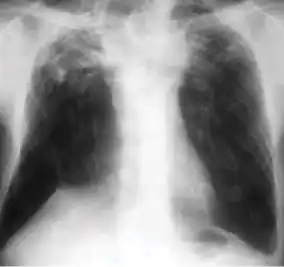

7. Other - Any other finding suggestive of active TB, such as miliary TB. Miliary findings are nodules of millet size (1 to 2 millimeters) distributed throughout the parenchyma.